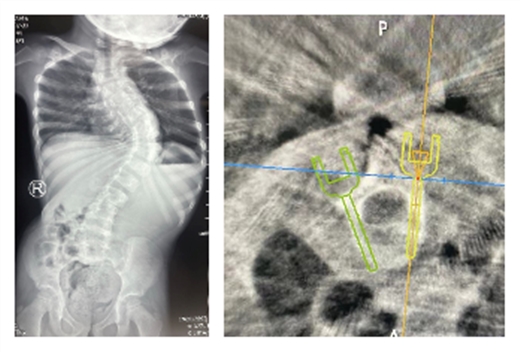

康学文主任对患儿病情极为重视,经详细查体、阅片,认为患儿脊柱畸形导致胸廓变形,如不及时手术干预,最终影响患儿心肺发育,甚至导致心肺功能衰竭。遂收住入院拟行手术治疗,考虑到患儿年龄小,发育差、椎弓根细小、椎体旋转畸形,常规徒手置钉存在很大风险,经过科室讨论后最终决定使用天玑机器人为患儿实施脊柱可调节生长棒植入术,这样既可以保证术中准确置钉,又不影响患儿术后脊柱生长发育。

8月4日,在麻醉科、手术室的精心配合下,天玑机器人通过快速扫描,测量患儿椎弓根粗细、规划椎弓根螺钉置入角度及深度,通过软件模拟置入,三维图像观察螺钉置入准确性并进行调整,选择适合长度粗细的椎弓根螺钉,设计完美的置入钉道,最后在手术机器人机械臂精确制导下按照软件预先设计的钉道逐个置入经过软件模拟测量的合适长度和粗细的螺钉。经过3个多小时的紧张奋战,成功在全麻下实施了天玑机器人辅助脊柱可生长棒调节置入术,术中机器人扫描后证实8枚椎弓根螺钉置入深度、角度均准确无误。术后在骨科二病区护理团队悉心护理下,患儿生命体征平稳,复查全脊柱正侧位片,获得预期满意的矫形效果,患儿于8月10日康复出院。